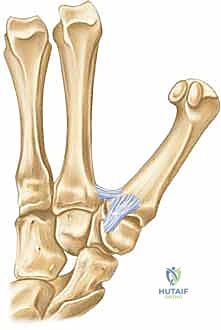

الأربطة الداعمة: حراس الاستقرار (Ligamentous Support)

نظراً لأن البنية العظمية للمفصل السرجي توفر حركة واسعة، فإنها تعتمد بشكل كبير على الأربطة القوية لمنع الخلع أو عدم الاستقرار. يتم الحفاظ على استقرار هذا المفصل الحيوي بواسطة شبكة معقدة من الأربطة، التي تعمل معاً كحبال خيمة مشدودة بدقة:

- الرباط الأمامي الراحي (رباط المنقار - Anterior Oblique / Beak Ligament): يُعد هذا الرباط الحارس الأول والأهم لاستقرار المفصل. ينشأ من الجانب الراحي للعظم المربعي ويدخل في الجانب الراحي الزندي لقاعدة المشط الأول. في حالات كسور "بينيت"، تظل شظية العظم الصغيرة متصلة بهذا الرباط، بينما يُسحب باقي العظم بعيداً.

- الرباط المائل الخلفي (Posterior Oblique Ligament): يقع في الجهة الظهرية ويعمل كرديف قوي لرباط المنقار في الحفاظ على التوازن.

- الرباط الكعبري الظهري (Dorsal Radial Ligament): يوفر دعماً وحماية ضد القوى التي تدفع الإبهام للخلف.

- الأربطة بين المشطيات (Intermetacarpal Ligaments): تربط قاعدة المشط الأول بقاعدة المشط الثاني، مما يمنع تباعد الإبهام بشكل مفرط عن باقي اليد.